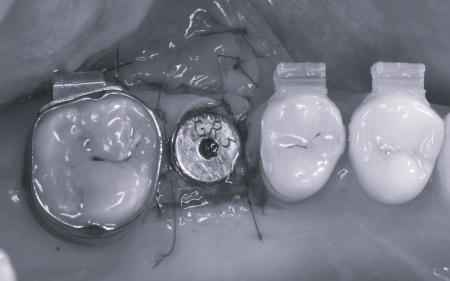

患者様は「健康な歯をできるだけ守りたい」との理由から、③のインプラント治療を希望されました。 まず、右上と左下の奥歯を抜歯しました。 矯正がある程度進んだ段階で、右上と左下のインプラント手術を実施しました。 インプラント手術後は矯正治療の仕上げを行い、装置を外しています。 治療終了後、下前歯の間に見られる三角形のすき間(ブラックトライアングル)が気になるとのご相談がありました。 |